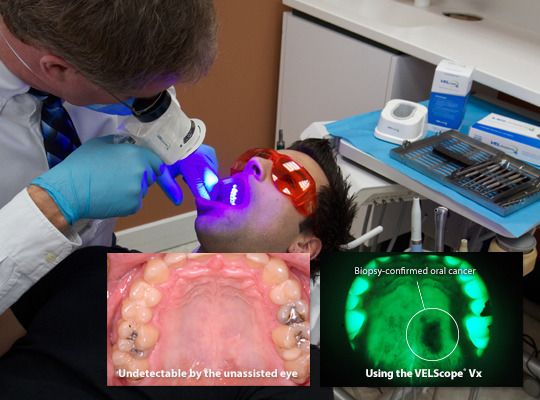

VELscope® Oral Cancer Screenings

Seventy percent of the time, oral cancer is not visible to dental professionals until the cancer has reached an advanced stage. The VELscope® technology enables Dr. Siegel to locate any abnormal tissue in the mouth very early. No rinses are necessary and the screening method is simple.